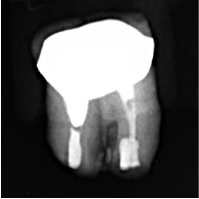

⑥充填を確認し元の位置へ戻す

レントゲンを撮影し、MTAセメントが充填されていることを確認します。問題がなければ、抜いた歯を元の位置に戻して、治療は完了です。